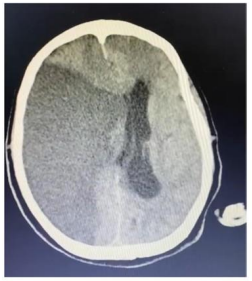

Um paciente de 76 anos de idade deu entrada na UPA, já fora de janela para trombólise, e foi posteriormente encaminhado para a UTI. A imagem apresentada refere-se à tomografia de admissão na UTI.

Um paciente de 76 anos de idade deu entrada na UPA, já fora de janela para trombólise, e foi posteriormente encaminhado para a UTI. A imagem apresentada refere-se à tomografia de admissão na UTI.